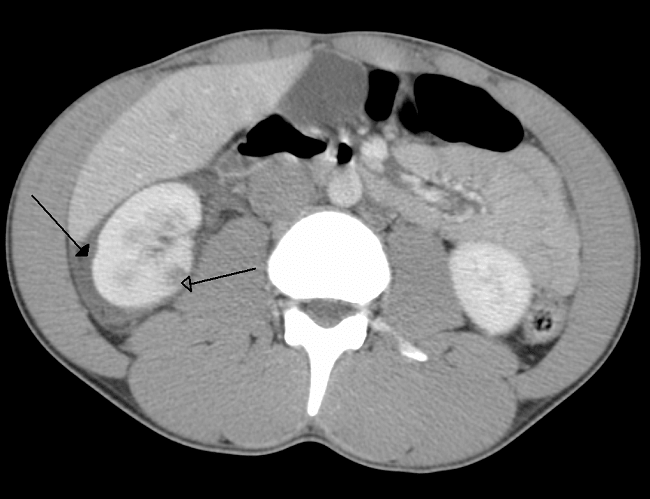

Salah satu modalitas yang dapat digunakan pada manajemen nonoperatif trauma tumpul limpa adalah angiografi/angioembolisasi (AG/AE). Haan et al. menyarankan bahwa indikasi AG/AE adalah pseudo-aneurisma (perdarahan aktif saat kedatangan) yang dilakukan CT scan, hemoperitoneum yang signifikan, dan cedera limpa tingkat tinggi.[14]

Lebih dari 80% cedera limpa sesuai AAST derajat IV-V berhasil ditangani secara non operasi dengan AG/AE. Pada sebuah studi multisenter berskala besar pada 10.000 pasien, didapatkan hasil bahwa AG/AE dikaitkan dengan penurunan kemungkinan splenektomi dan pada pasien yang semakin awal dilakukan AG/AE, semakin sedikit yang menjalani splenektomi.[14,15]

Beberapa studi meta analisis menunjukkan peningkatan yang signifikan dalam keberhasilan manajemen nonoperatif setelah pengenalan protokol AG/AE (OR 0,26, 95% CI 0,13-0,53, p <0,002). Angka kegagalan tanpa AG/AE secara signifikan lebih tinggi dibandingkan dengan AG/AE pada cedera limpa sesuai AAST derajat IV dan V (43,7% dibanding 17,3%, p = 0,035, dan 83,1% vs. 25,0%, p = 0,016, pada masing-masing derajat).[16,17]